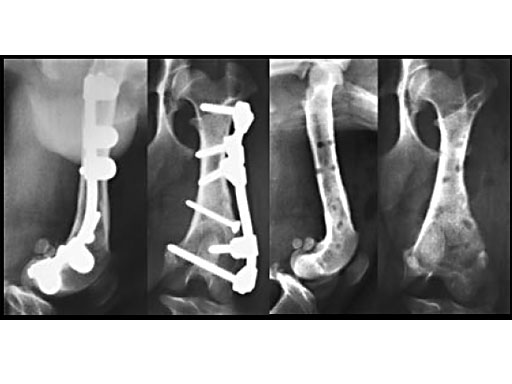

Clinical application in small animals: A 1-year-old female Dachshund was admitted with a transverse fracture in the distal metaphysis of the femur. Fixation was accomplished with a 2 mm interfragmentary screw in a lag fashion and a 2.7 mm VetFix with five screws. The fracture healed and the implants were removed four months postoperatively. The benefit of the VetFix can be shown on this breed of dog, the females of which do not have one straight bone in their body. The rod was contoured along the bone, which is not possible with a plate.

1-year-old Dachshund

(Case provided by K. Zahn and U. Matis, Munich, Germany)